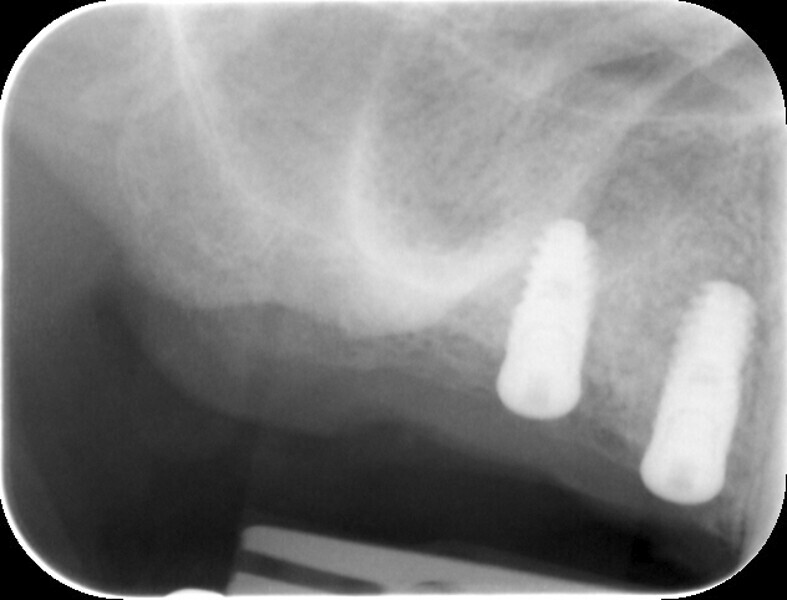

Fig. 11: Post-op radiograph of the implants.